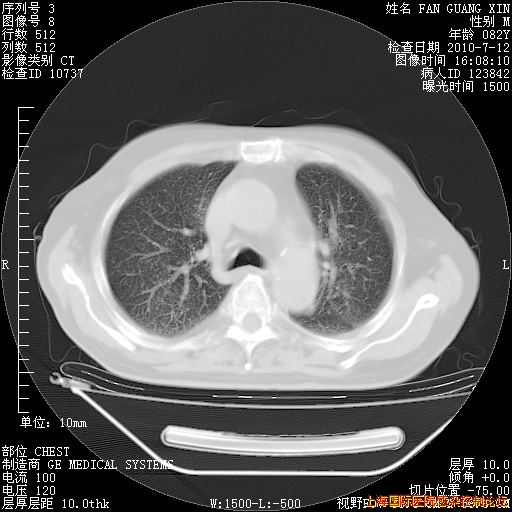

今天复查CT

今天CT

整整相隔30天的肺部CT好像有所好转啊。甲强龙减量第3天,需要观察体温。

海管,自昨日你和我通完话后,不知您岳父消化道症状有无缓解?体温怎样?阅读7.12日胸部ct,个人认为目前激素治疗是有效的,甲强龙减量是适宜的。因在抗痨治疗,需密切观察肝功、肾功能和血常规。不过,老年、长期住院和大量使用激素,很担心菌群失调发生